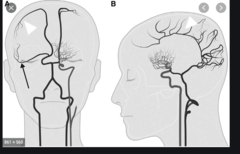

blood vessel anatomy

Front

Back